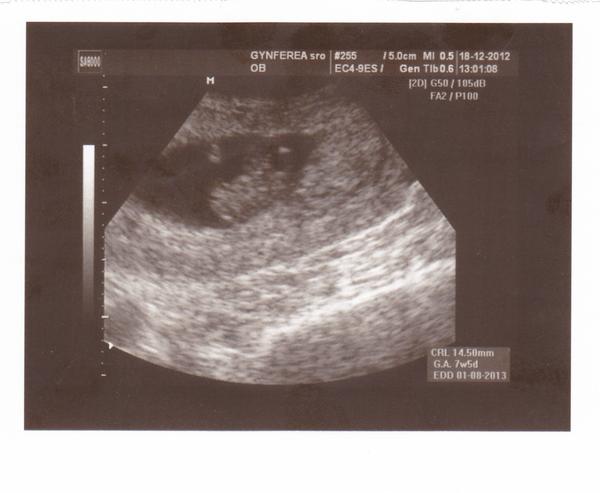

nase mimi 😵 😵 7+5tt, 14,5 mm 😵 😵 dnesne sono